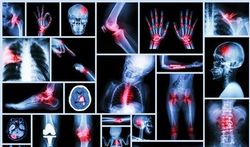

L’imagerie par résonance magnétique (IRM) permet de voir des choses extraordinaires à l’intérieur de notre corps.

Sa fonction première est de nature médicale, bien sûr, en particulier pour affiner le diagnostic. Mais elle présente un autre intérêt : dans la mesure où il n’y a pas d’émission de radiations nocives, cette technique peut être utilisée sans danger pour observer des mécanismes assez banals, mais très insolites vus de cette manière, comme le passage d’un jus de fruit dans la gorge, le mouvement de la langue d’un joueur de cor, l’excitation au moment d’un baiser, la vibration des cordes vocales ou le face-à-face de jumeaux dans le ventre de maman. On perçoit vraiment la vie autrement.